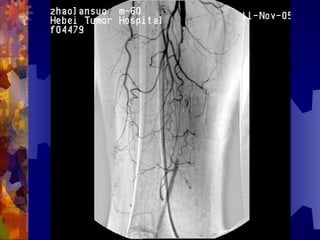

糖尿病足的检查

4. 足部 X- 线检查

5. 动脉造影(下肢)

6. 溃疡表面分泌物的培养

男, 86 岁

双下肢多普勒血流图未探及血管

动脉造影血管闭塞